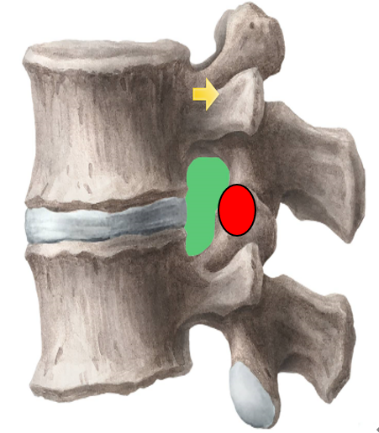

为解决以上问题���,我们提出“椎间孔镜按需成型5级法”��,即将椎间孔镜术中椎间孔成型的实际操作范围进行分级���:0级����:不成型����,见图 1��;1级���:软组织成型�����,只去除关节囊等部分软组织�����,基本不做骨性成型���,见图 2���;2级�����:少许骨质成型���,但不显露下关节突关节面����,见图 3����。3级成型�����:上关节突尖部或上1/2去除成型���,显露下关节突关节面���,见图 4�����;4级成型����:上关节突大部分成型或伴有部分椎弓����、峡部或下关节突小部分���,但预留基底部一部分��,见图 5��。

2���、建立五级成型的有限元模型

正常腰椎模型命名为M0���;0级成型为M1��:不做骨性成型���;1级成型为M2���:软组织成型����,只去除关节囊等部分软组织���,基本不做骨性成型��;2级成型为M3����:少许骨质成型��,不显露下关节突关节面����;3级成型为M4a与M4b���:上关节突尖部(M4a)或上1/2(M4b)去除成型���,显露下关节突关节面����;4级成型为M5�����:上关节突大部分成型或伴有部分椎弓���、峡部或下关节突小部分�����,但预留基底部一部分���,见图16-20���。每组模型都按照前屈����、后伸���、左屈����、右屈���、左旋及右旋6种状态加载��,其他约束条件不变���,观察各组成型对于腰椎活动度及椎间盘应力的影响���。